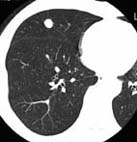

CaseKS08

Case A

X-ray CT